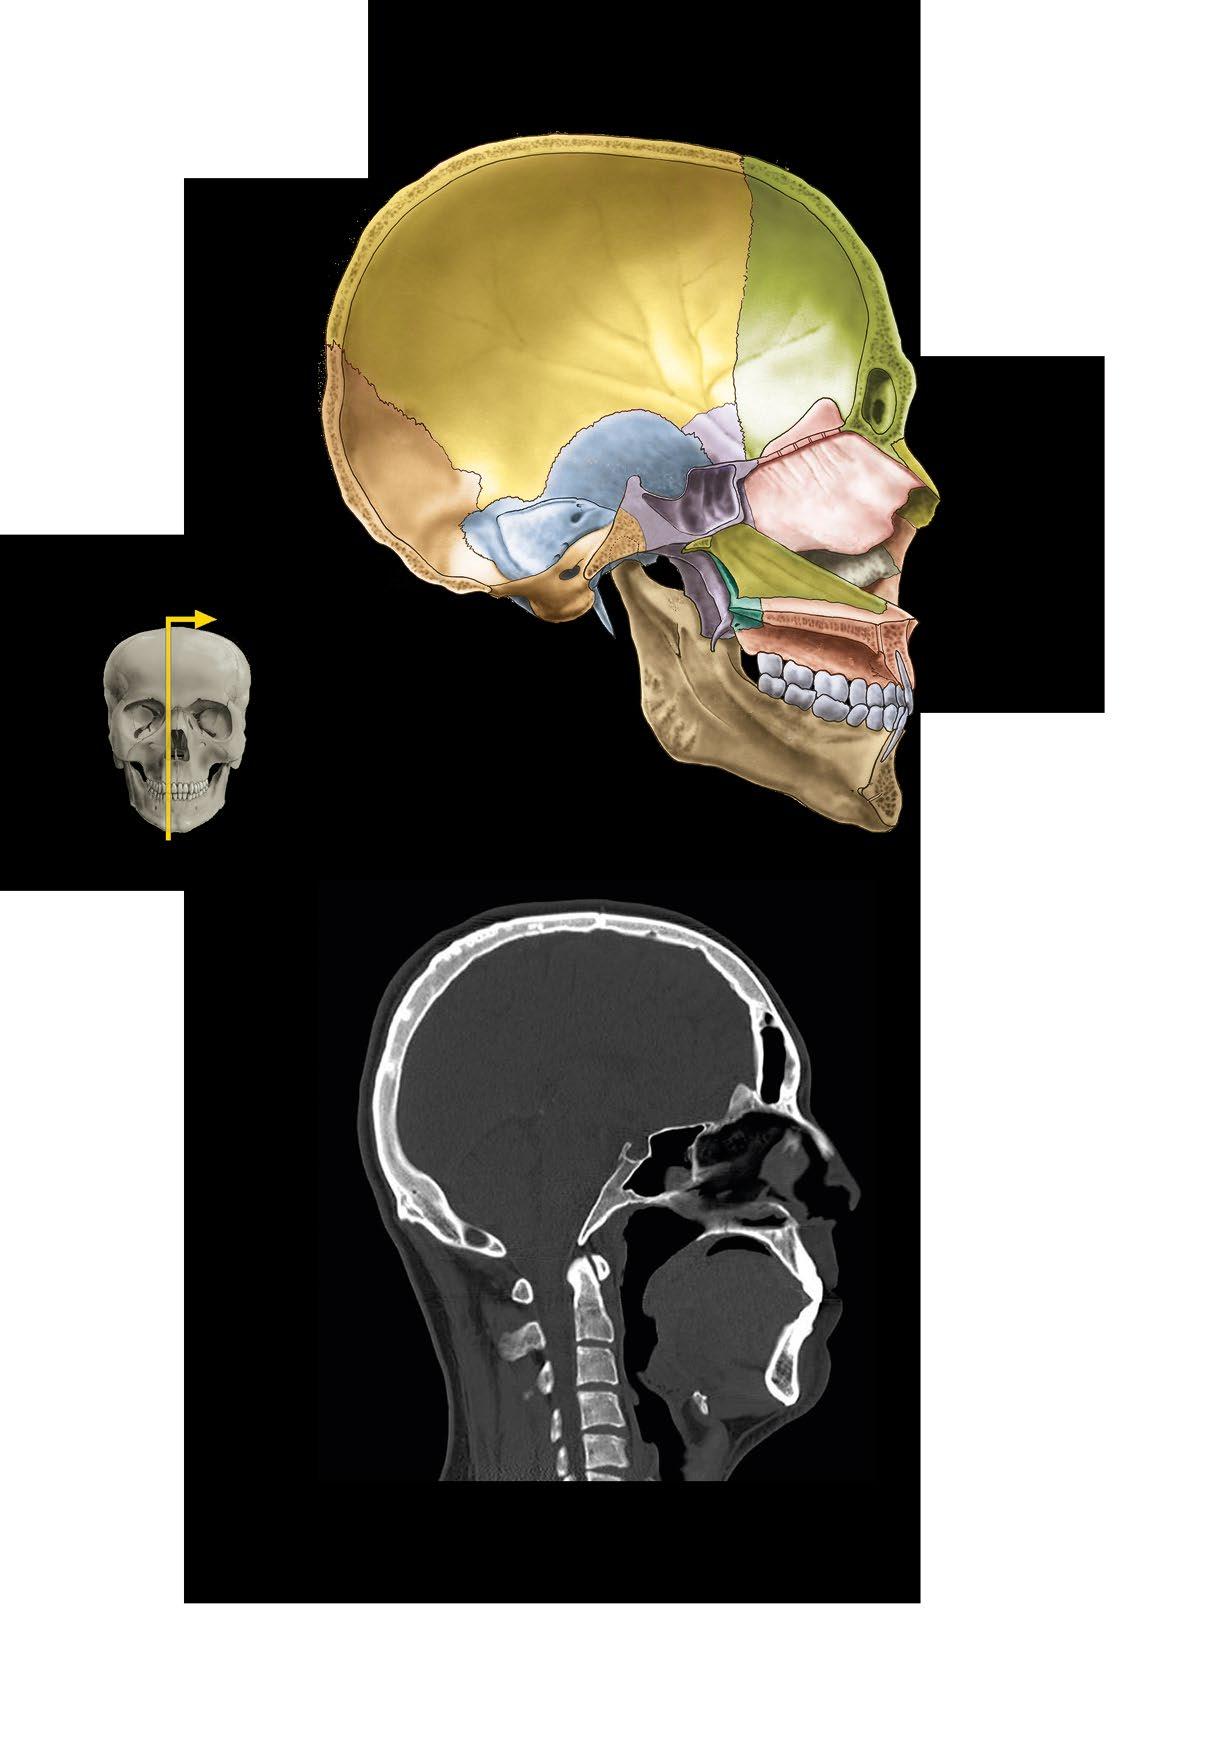

os parietale

os sphenoidale

os lacrimale os nasale vomer

os occipitale os temporale

Ossa cranii, kosti lebky

a pohled zpředu

b pohled zboku

Bones of the skull

a frontal view

b lateral view

os frontale os temporale os zygomaticum os ethmoidale, concha nasalis media

concha nasalis inferior mandibula

os frontale

os ethmoidale os ethmoidale os lacrimale os nasale os zygomaticum

os temporale

os zygomaticum

os occipitale

praemaxilla

maxilla os palatinum

Basis cranii externa et interna

a zevní plocha base lební

b vnitřní plocha base lební

c členění vnitřní plochy base

fossa cranii posterior

External and internal base of the skull

a external surface

b internal surface c cranial fossae

a Sagitální řez lebkou b CT lebky v sagitální rovině

os palatinum

maxilla

sella turcica sinus sphenoidalis

os nasale lamina perpendicularis ossis ethmoidalis/ septum nasi

concha nasalis inferior vomer

sinus frontalis

pharynx

mandibula os hyoideum

a Sagittal section of the skull b CT of the skull in sagittal plane